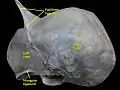

Triangular ligament of liver.Superior surface of liver. Triangular ligament of liver.Superior surface of liver.

Triangular ligament.Diaphragmatic surface of liver. Triangular ligament.Diaphragmatic surface of liver.